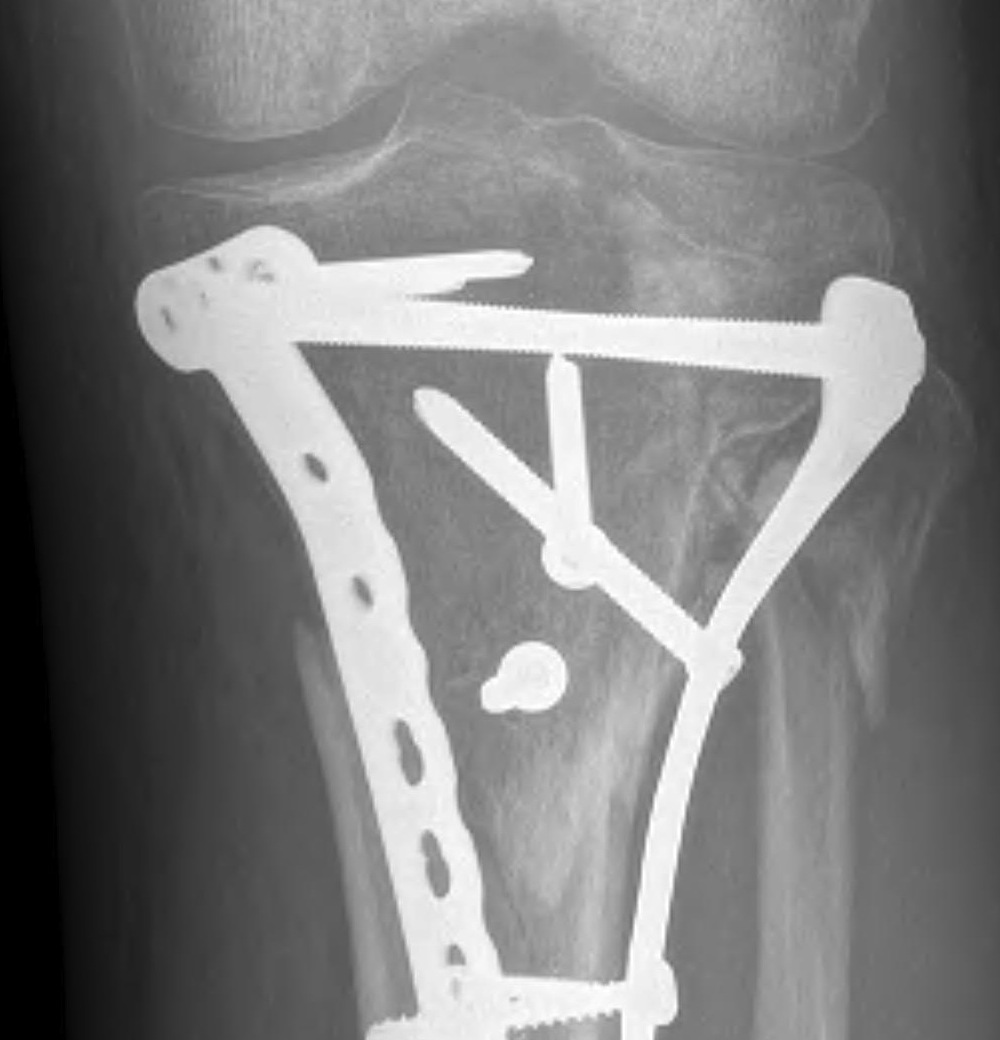

Type V Bicondylar

Options

1. Medial and Lateral plating

Technique

- depends on which of the three columns affected

- anterolateral approach for lateral column

- posteromedial appraoch for medial / posterior column